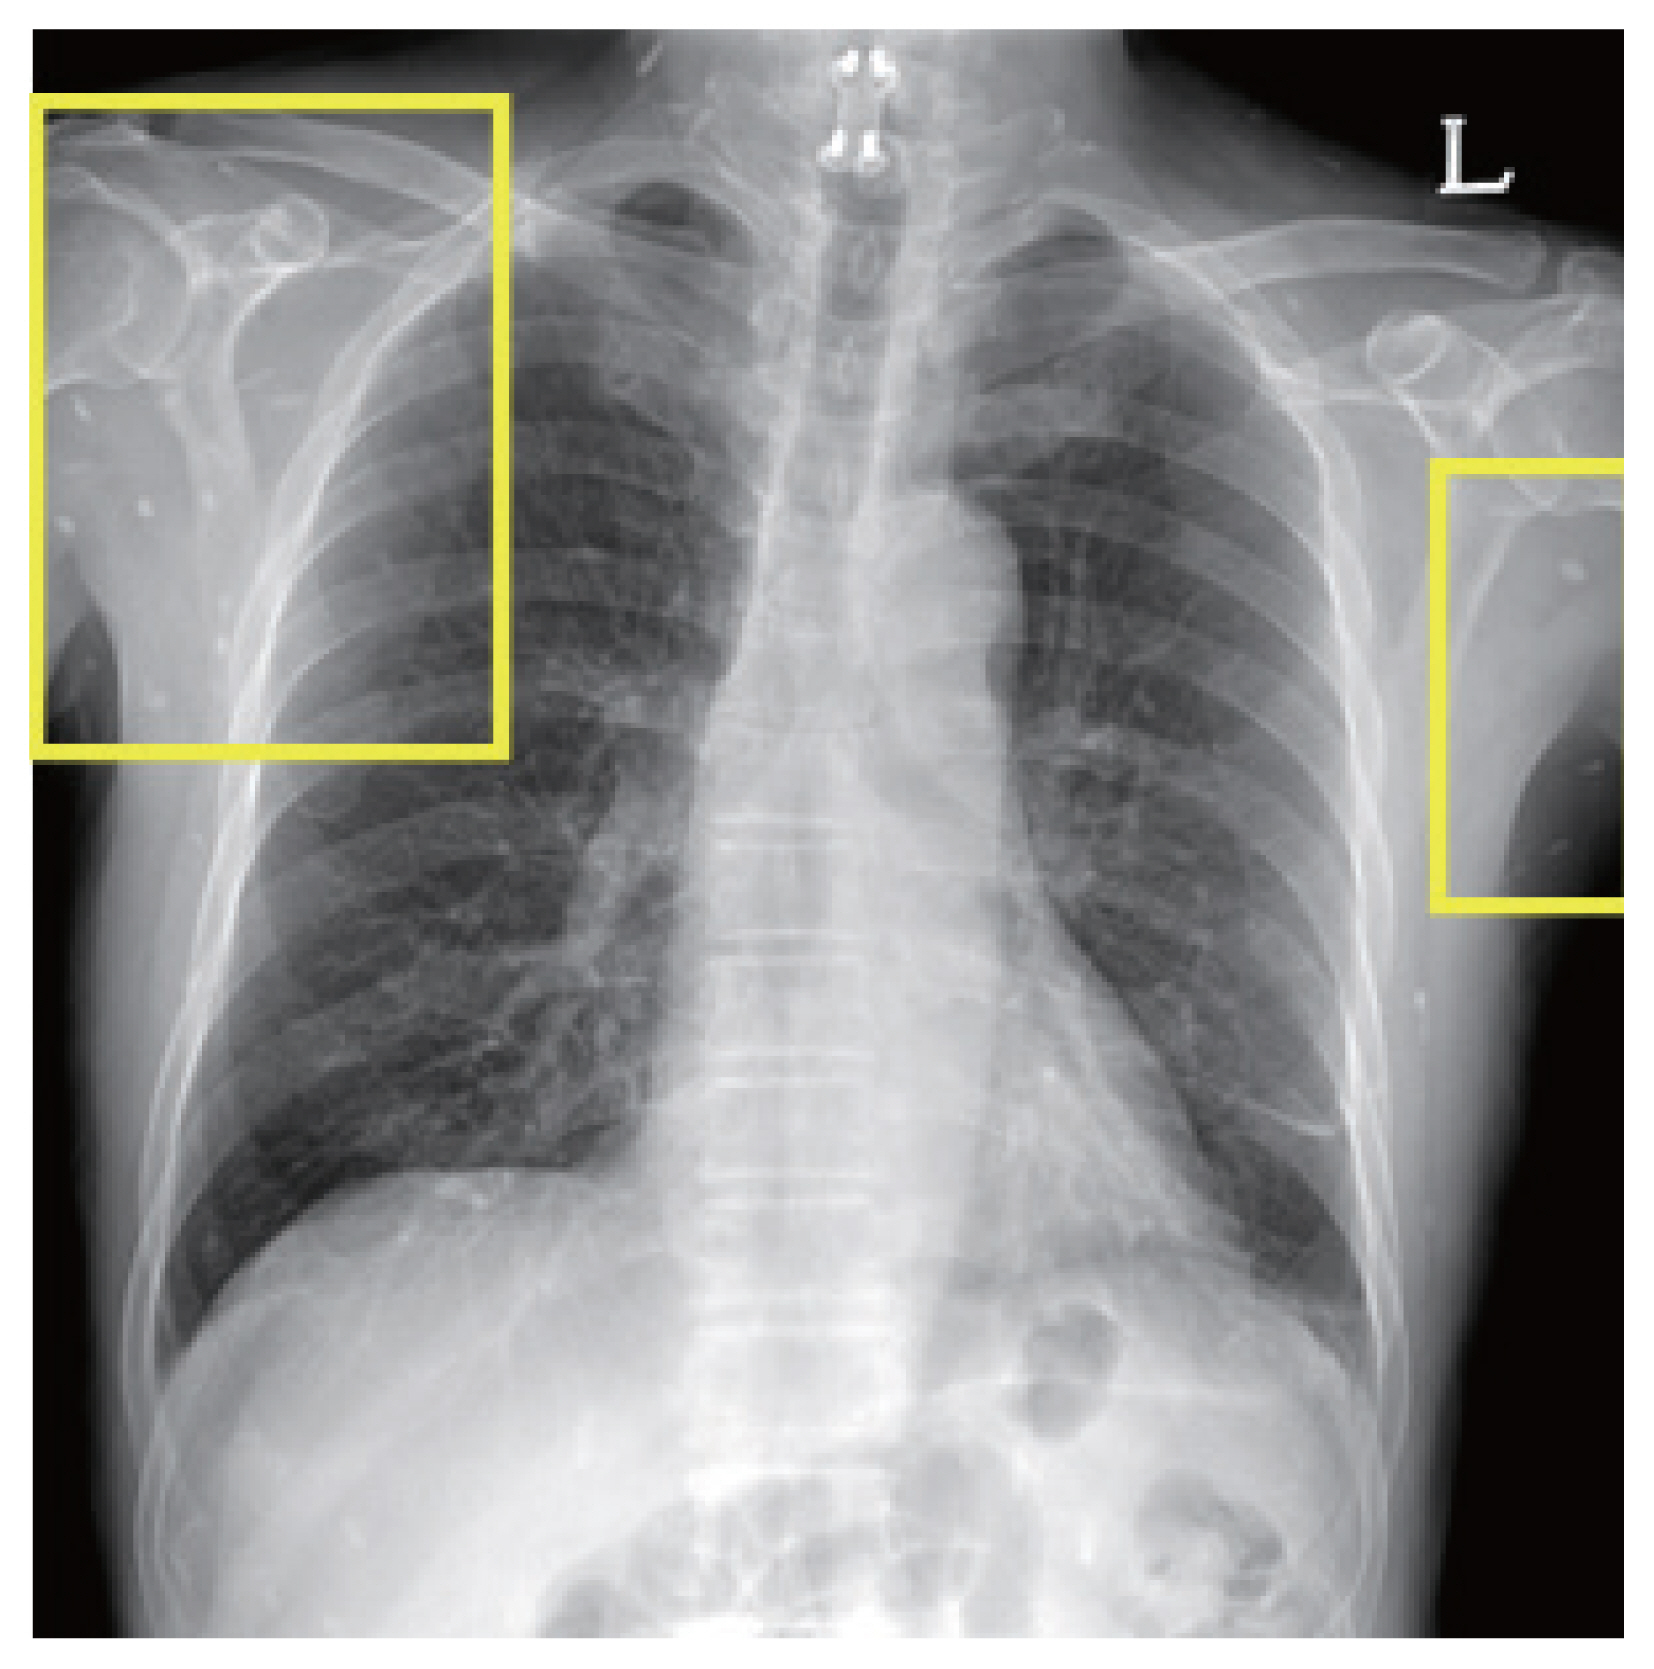

One of the patients was a 66 year old male with no previous medical history, who was admitted with symptoms of headache, vertigo, and gait disturbance. He had a history of working in Libya 35 years ago, and a history of travel to Vietnam (4 years ago) and China (1 year ago). CSF findings showed eosinophilic pleocytosis (CSF white blood cell count 29/μl, eosinophil percentage 18%), with elevated protein levels (89.3 mg/dl) and normal glucose levels (56 mg/dl). Brain MRI showed multiple cystic lesions with focal wall enhancement at both frontal base and subcallosal areas, with ventriculomegaly of both lateral ventricles and the 3rd ventricle (Fig. 1). Multiple calcific nodules in soft tissue were seen on chest imaging (Fig. 2). Based on these findings, immunodiagnostic testing for parasite infections were performed on the patient’s blood and CSF. Both serum and CSF cysticercus antibodies were positive, and the patient was diagnosed with neurocysticercosis. Albendazole was administered for 4 weeks, in combination with dexamethasone. Afterwards, his symptoms of headache improved, but his limping gait worsened, leading to a second course of therapy with albendazole, praziquantel, and steroids 3 months after the initial treatment. The patient showed slight improvement in symptoms before he was transferred to another hospital, and follow-up was lost.